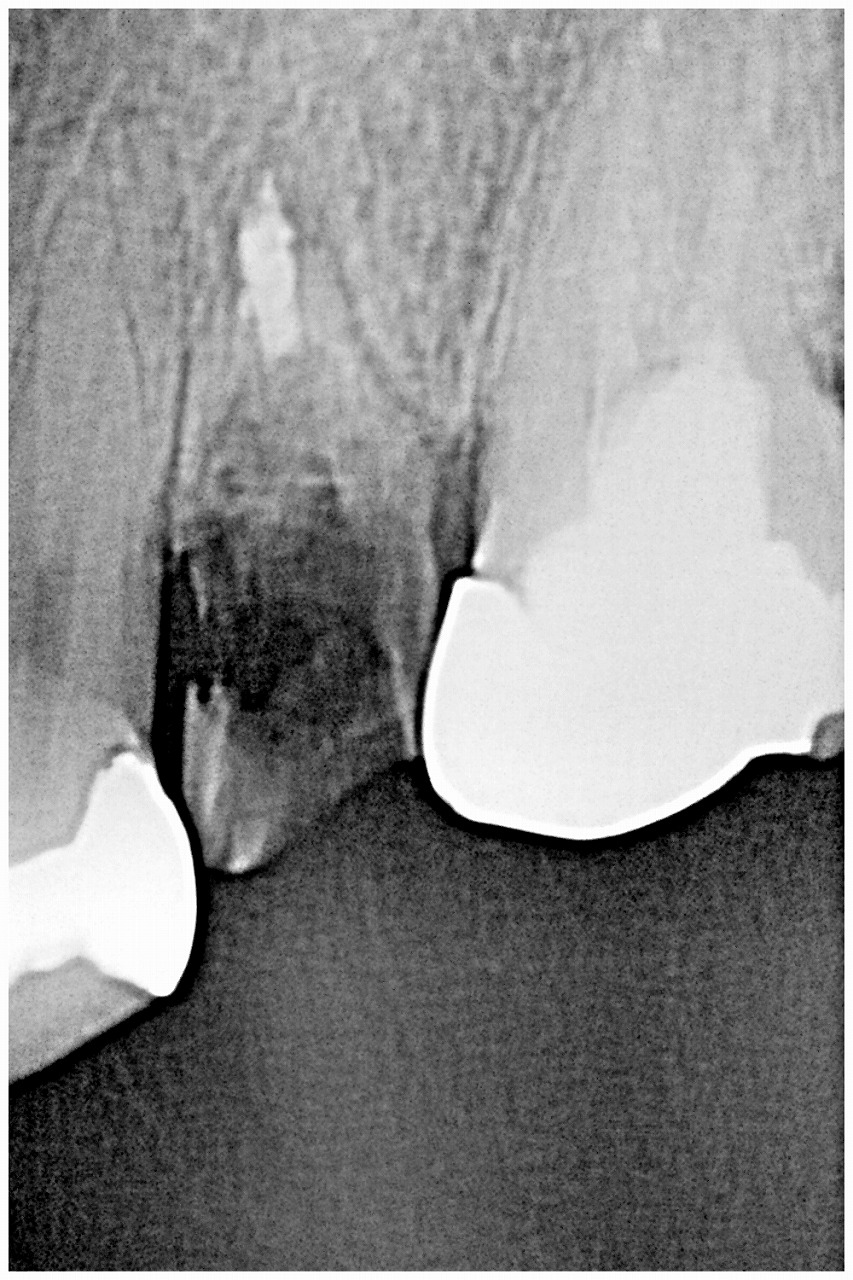

デンタルレントゲンになります

確かに抜歯の歯でした